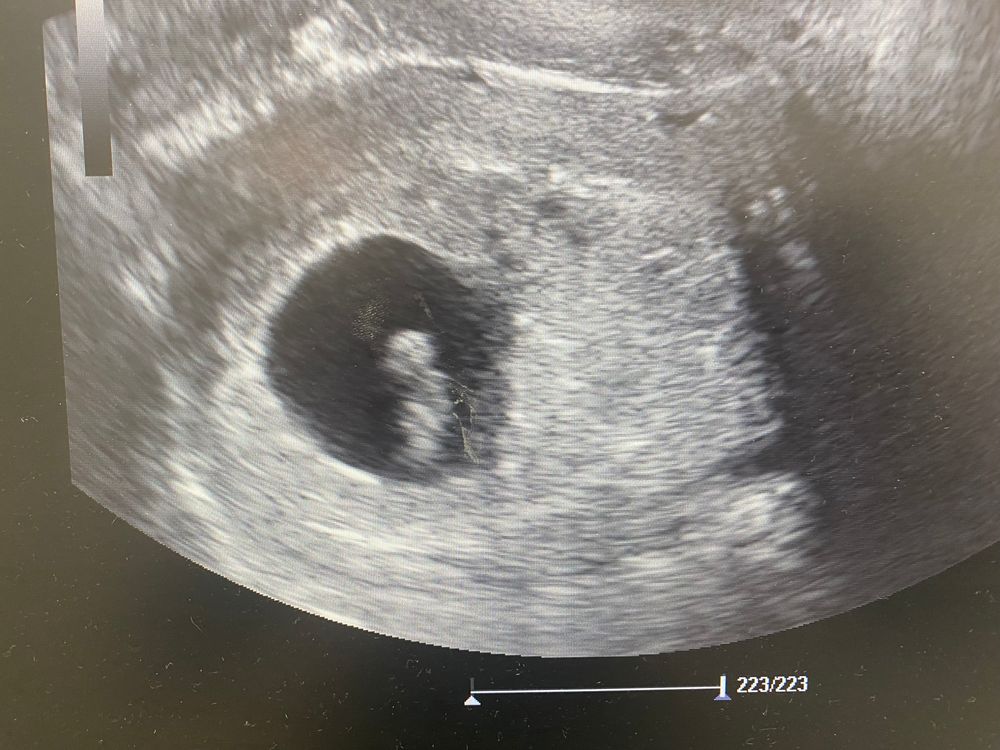

7 недель беременности. Увидела сердцебиение и эмбриончик на УЗИ😍

Вчера сходила в ЖК, мне сделали УЗИ, срок 6 недель и 6 дней. Как я рада была увидеть его на экране и увидеть как бьется его сердечко💗